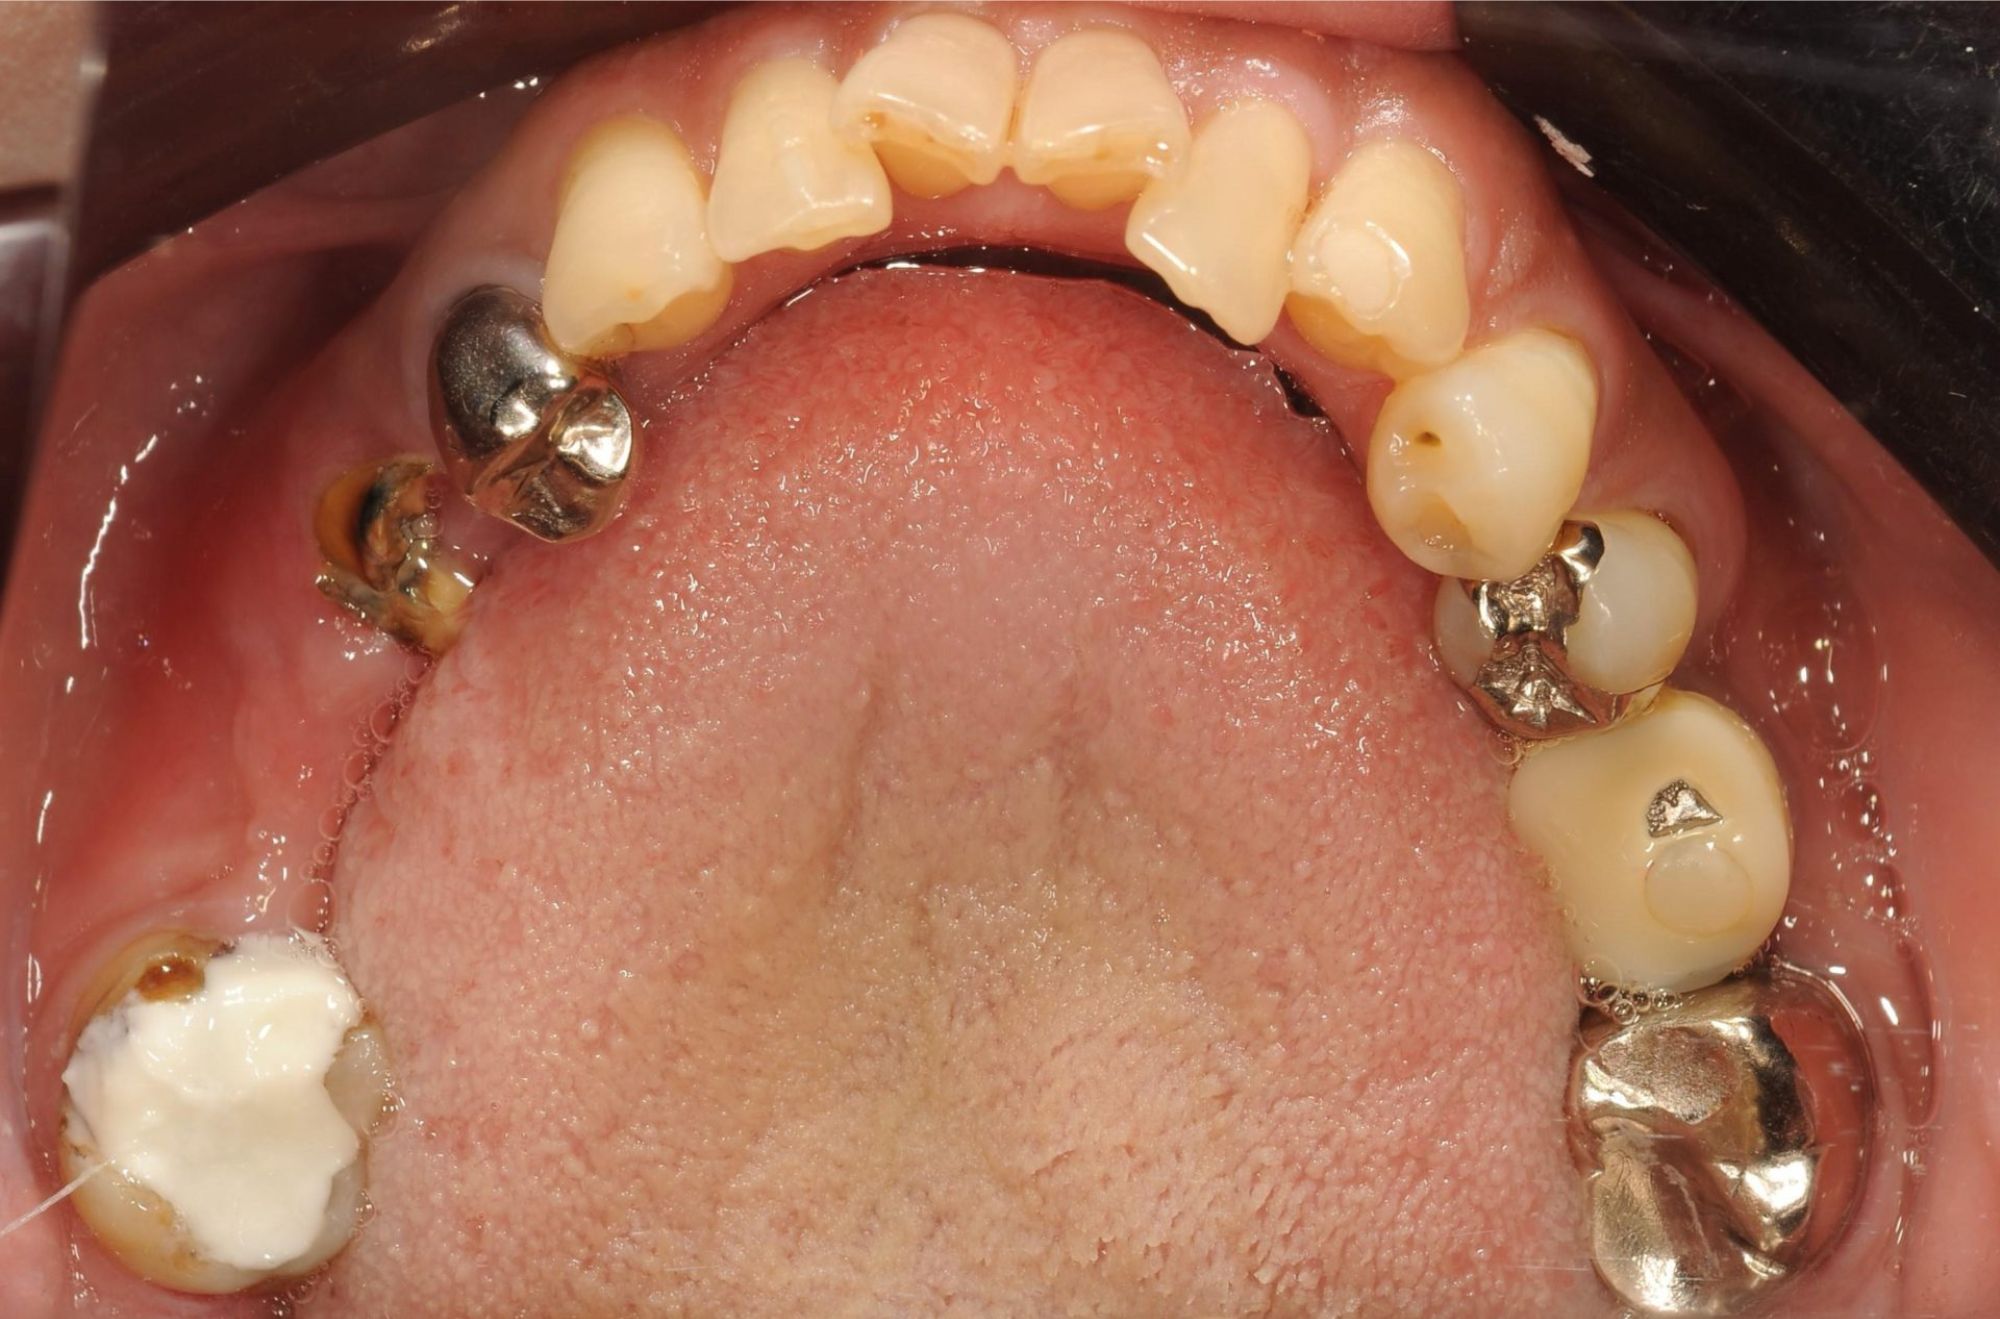

case.02

差し歯とインプラントの治療

若年の患者様が前歯の審美性について相談に来られました。差し歯とインプラントの組み合わせにより、自然で美しい笑顔を実現しました。患者様は見た目の改善と機能性の向上に大変満足されました。